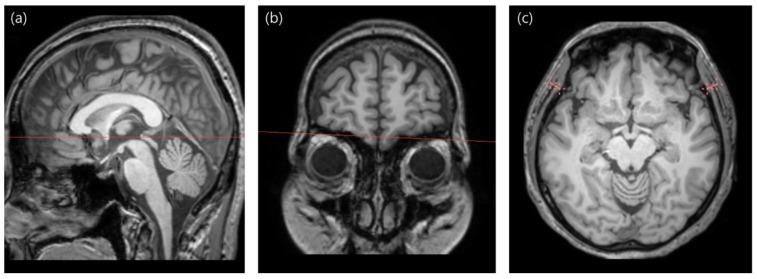

Sarcopenia, characterized by progressive muscle loss and functional decline, poses significant risks, including falls, impaired daily activities, and increased mortality. We developed Allgeun, a novel device that measures handgrip strength, muscle mass, and physical performance. This study aimed to investigate whether temporal muscle thickness (TMT) could be used as a sarcopenia marker and to evaluate the usability of Allgeun. This prospective study enrolled 28 participants without medical or neurological disorders. They underwent three-dimensional T1-weighted imaging using a 3 Tesla magnetic resonance imaging scanner. TMT was measured based on T1-weighted images by a board-certified neuroradiologist. Allgeun was used to measure the following three key components of sarcopenia: muscle strength (handgrip strength), muscle mass (calf and thigh circumference), and physical performance (five times the chair stand test). Correlation analysis was conducted between TMT and the results of the handgrip strength, calf and thigh circumferences, and chair stand tests. There were moderate positive correlations between TMT and calf circumference (r = 0.413, = 0.029), thigh circumference (r = 0.486, = 0.008), and handgrip strength (r = 0.444, = 0.018). However, no significant correlation was observed between TMT and physical performance (r = -0.000, = 0.998). Our findings underscore TMT's potential as an indicator of sarcopenia, particularly regarding muscle mass and strength. Additionally, we demonstrated that the new device, Allgeun, is useful for screening and diagnosing the severity of sarcopenia.

肌肉减少症以肌肉逐渐流失和功能衰退为特征,会带来重大风险,包括跌倒、日常活动受损和死亡率增加。我们开发了Allgeun,这是一种可测量握力、肌肉质量和身体机能的新型设备。本研究旨在调查颞肌厚度(TMT)是否可作为肌肉减少症的标志物,并评估Allgeun的可用性。这项前瞻性研究招募了28名无医学或神经疾病的参与者。他们使用3特斯拉磁共振成像扫描仪进行了三维T1加权成像。由一名获得委员会认证的神经放射科医生根据T1加权图像测量TMT。Allgeun用于测量肌肉减少症的以下三个关键组成部分:肌肉力量(握力)、肌肉质量(小腿和大腿周长)和身体机能(五次起坐试验)。对TMT与握力、小腿和大腿周长以及起坐试验结果进行了相关性分析。TMT与小腿周长(r = 0.413,P = 0.029)、大腿周长(r = 0.486,P = 0.008)和握力(r = 0.444,P = 0.018)之间存在中度正相关。然而,未观察到TMT与身体机能之间存在显著相关性(r = -0.000,P = 0.998)。我们的研究结果强调了TMT作为肌肉减少症指标的潜力,特别是在肌肉质量和力量方面。此外,我们证明了新设备Allgeun可用于筛查和诊断肌肉减少症的严重程度。